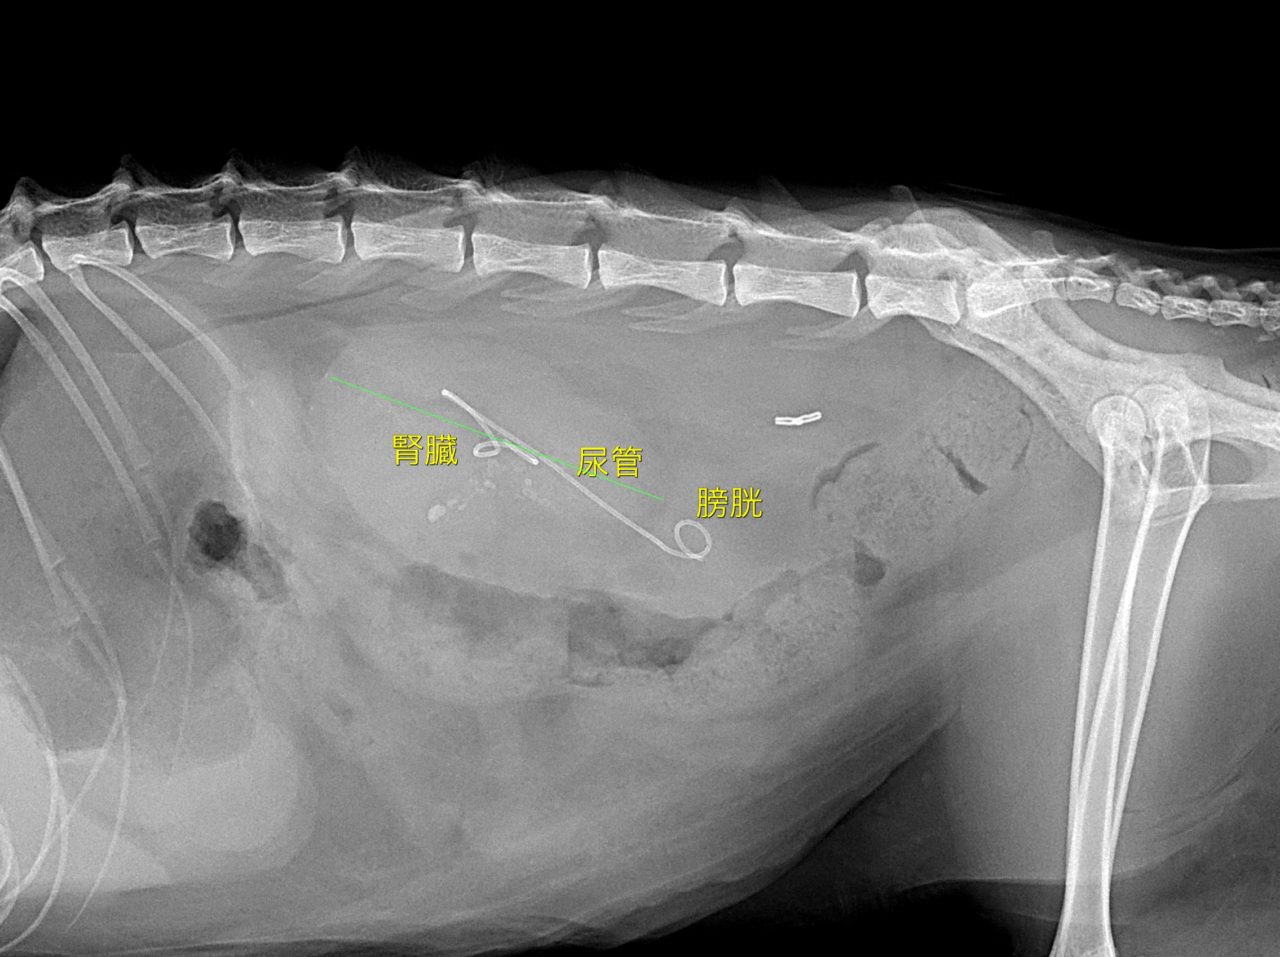

急性腎機能障害の猫ちゃんが(BUN>130mg/dl、Cre>14mg/dl、高カリウム血症)治療のため救急で対応しました。無麻酔CTでは両側に尿管結石が確認されました。著しく拡張している左腎の腎盂に一時的な腎瘻カテーテルを設置し、尿の排泄路の確保を行います。しかし、腎数値に改善は見られませんでした。腎盂造影を行うと拡張している腎臓において尿の産生と排泄は行われている様です。一方、腎盂拡張のほとんどない右腎の腎盂造影では尿の排泄が確認されません。今回の急性腎機能障害の原因は機能の残っていた右腎の急性尿管閉塞による急性腎障害と診断しました。左腎に関しては尿の産生はあるものの慢性腎機能障害であり、すでに尿濃縮能は失われていると判断しました。右腎の問題に対して尿管膀新吻合短尺型ステント設置術を行いました。術後は徐々に腎数値は低下し、腎機能の回復が得られました。一見すると腎盂拡張の顕著な側が急性腎障害の責任病変と判断しがちですが、片腎が十分に機能していれば腎数値に影響はほとんどなく、どちらの腎臓を治療対象とするか?エコー、CTなどの画像診断、血液検査、一時的な腎瘻カテーテルの設置、腎盂造影など総合的な判断が必要です。また判断がつかず、左右同時に治療が必要な場合もあります。